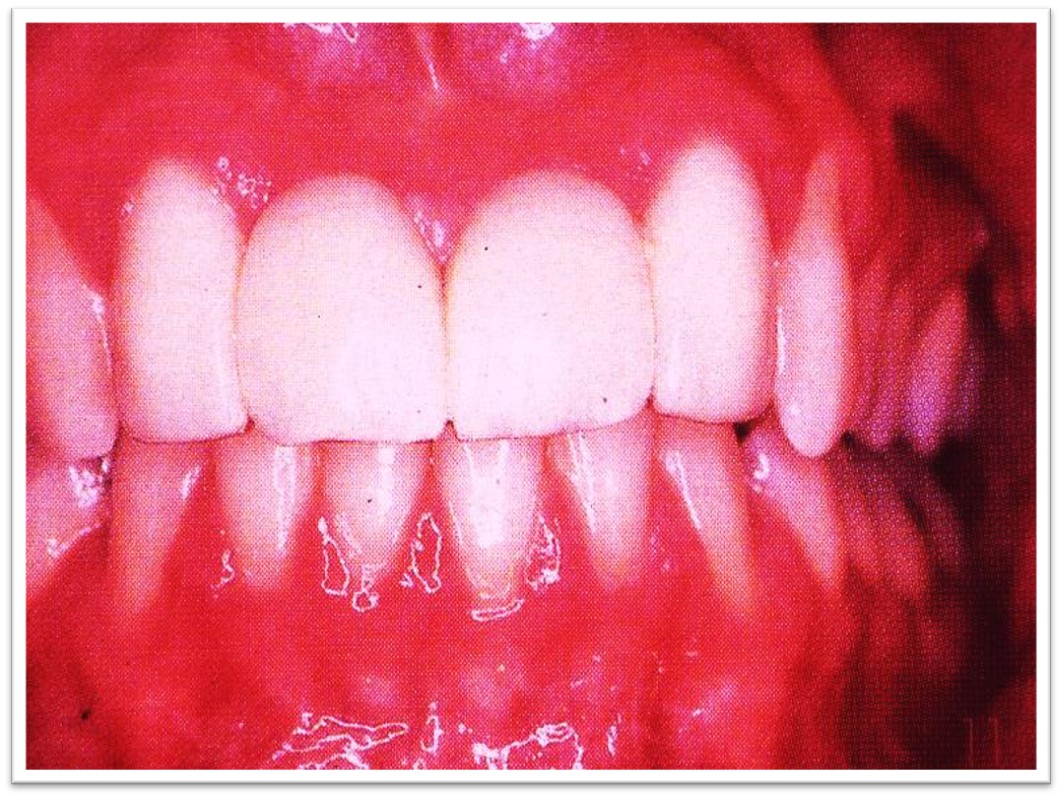

3)浆细胞龈炎( plasma cellgingivitis)

②临床表现

见于年轻女性。

病变部位红肿、光亮(图10.1-9),也可呈现小结节或颗粒肉芽肿状。

图10.1-9 浆细胞龈炎